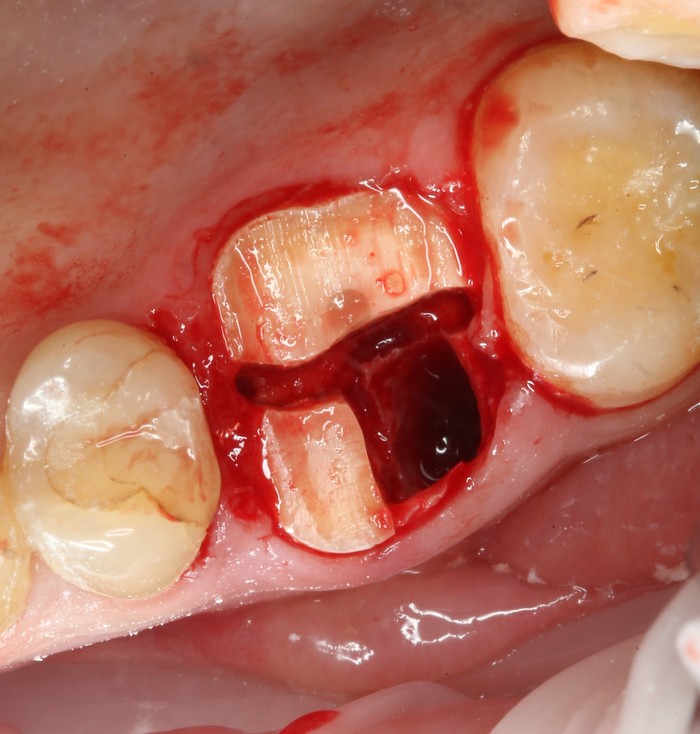

После снятия коронки:

Выкрутили абатмент:

Установлена заглушка, которая закрывает шахту имплантата.

Теперь необходимо выждать около 2-х месяцев для того, чтобы десна восстановилась (Пациентка это время ходила со специальной капой, которая имитирует наличие зуба).